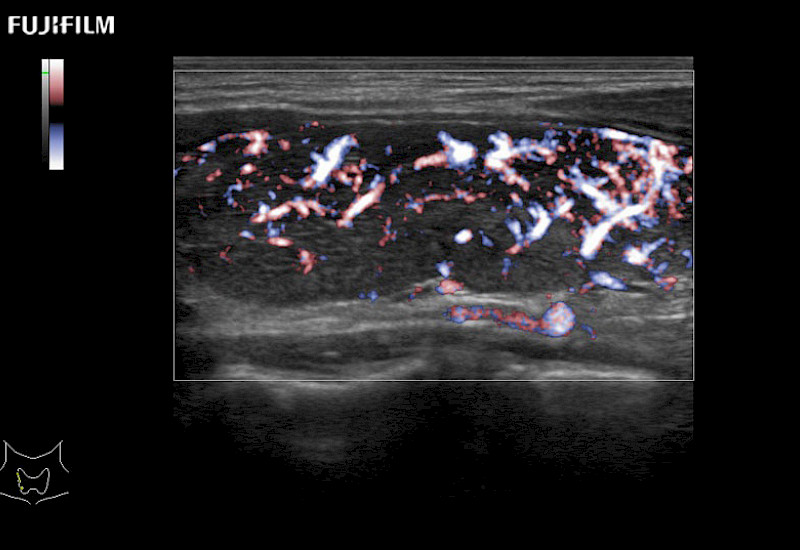

Extraordinary high-resolution digital imaging

Multi-Parametric imaging modalities